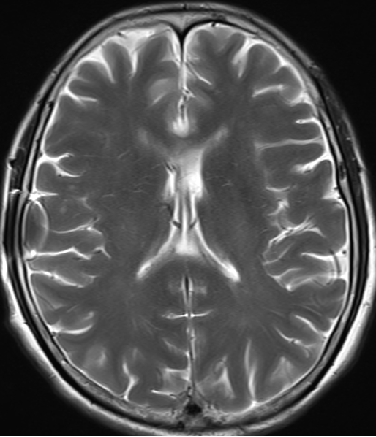

2014-10-17 CT

仍时有前额部疼痛,程度轻,调压190—200